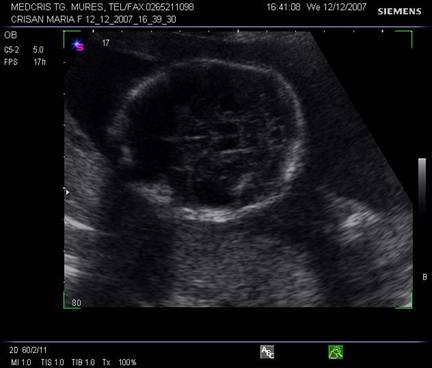

Planul V - trece prin partea bazala a mezencefalului si emisferele cerebrale. Pedunculii cerebrali formeaza aspectul de fluture, intre acestia apare fosa interpedunculara.

Fig. nr. 153. Planul V de sectiune transversala